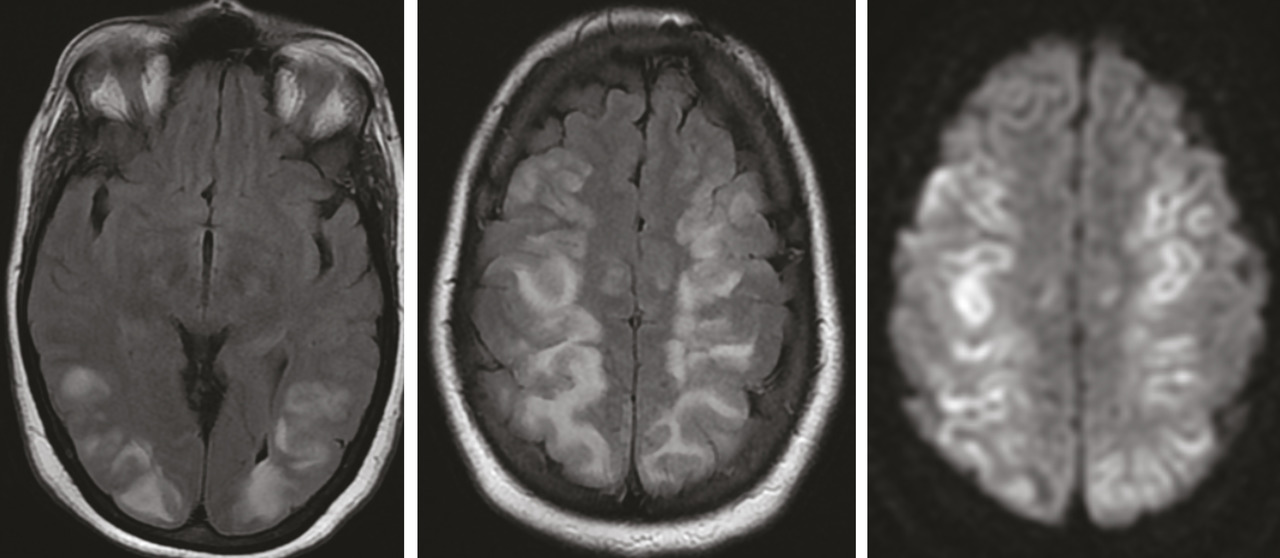

Cette femme de 36 ans avait une hypertension artérielle à 200/100 mmHg et une monoparésie du membre supérieur gauche post-critique, dans le cadre d’une toxémie gravidique. Une IRM encéphalique mettait en évidence des anomalies de signal cortico-sous-corticales et profondes, bilatérales et symétriques, prédominant aux lobes postérieurs, en iso- à hyposignal T1, hypersignal T2, Flair et diffusion avec un coefficient de diffusion apparent bas ; il n’y avait pas de prise de contraste après injection du gadolinium et pas d’anomalie de calibre des artères du polygone de Willis à l’analyse de la séquence d’angio-IRM en temps de vol (figure) . Le diagnostic était celui d’encéphalopathie postérieure probablement réversible. L’évolution était effectivement favorable, avec normalisation sous traitement de la pression artérielle. Deux mois plus tard, l’IRM montrait une disparition complète sans séquelles parenchymateuses cérébrales.

La leucoencéphalopathie postérieure réversible est une entité clinico-radiologique récemment individualisée.1 Les facteurs favorisant sa survenue sont dominés par les situations où il existe une élévation de la pression artérielle.1, 2 Les données de l’imagerie tomodensitométrique (TDM) et/ou par résonance magnétique (IRM), souvent caractéristiques, traduisent un œdème vasogénique. En TDM, l’atteinte est marquée par des hypodensités diffuses. En IRM, les lésions apparaissent en iso- ou hyposignal T1 et hypersignal T2 et Flair. L’imagerie de diffusion montre une augmentation du coefficient de diffusion. Il n’y a habituellement pas de rehaussement après injection de produit de contraste. Cette atteinte cortico-sous-corticale et profonde siège préférentiellement dans les régions postérieures (lobes pariétaux ou occipitaux dans 98 % des cas).3 L’évolution est généralement favorable sans séquelles sous traitement précoce et rapide visant à contrôler la pression artérielle et sa cause.4